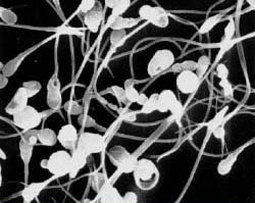

A young married couple cannot conceive. After a series of different tests, one of which is the analysis of a sperm sample, it is found that the sperm hardly move and that no fructose is present in the ejaculate. Their doctor diagnoses an abnormality of the seminal vesicles which is indicated by the absence of fructose in the ejaculate.